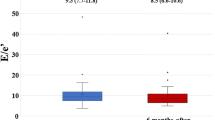

Only three studies were found to investigate the changes in echocardiography by SGLT2 inhibitor treatment, all of which were single-arm studies [27,28,29]. No two-arm echocardiography study was found at the time of literature search. The results of these studies with SGLT2-inhibitors are listed in Table 2. LVMi was significantly reduced and diastolic function improved during treatment in all studies (Fig. 5), whereas LVEF was improved in only one study [29]. Similar reduction of LVMi was reported in a cardiac myocardial resonance imaging (CMR) study; 6-month treatment of empagliflozin reduced LVMi in T2DM patients with CAD compared with placebo, and the degree of reduction was greater in those with higher baseline LVMi [30]. As described above, SGLT2 inhibitors could reduce the risk of HF in patients with T2DM, whereas DPP4 inhibitors did not. The reduction of LV hypertrophy, which is not clear in studies with the DPP4 inhibitors, might play some roles in the HF prevention by SGLT2 inhibitors. Most of the echocardiographic studies with SGLT2 or DPP-4 inhibitors were of small scale and had limitations. Recently, it has been suggested that SGLT2 inhibitors may reduce the risk of both HHF and CV death in patients with HFrEF irrespective of the presence or absence of T2DM. It may make a hypothesis that the preventive effect of SGLT2 inhibitors on might not be related with the echocardiographic changes associated with T2DM. Large-scale RCT studies are required to clarify how SGLT2 inhibitors modify the structural and functional changes in the heart of T2DM patients, and whether or how these changes could be related to reduction of HF incidence.

Changes in left ventricular (LV) mass and diastolic function after treatment with an SGLT-2 inhibitor. Changes in LV mass index and lateral e′ velocity from baseline (Pre-EMPA) to the follow-up study (Post-EMPA) after 3 months treatment with empagliflozin, an SGLT-2 inhibitor, in 10 patients with T2DM and established cardiovascular disease [27]